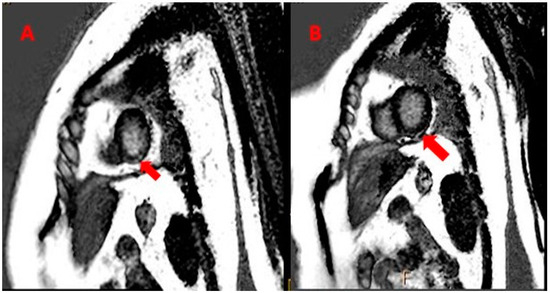

On 19 December 2017, a biopsy of the nevus revealed metastatic malignant melanoma and a subsequent total body PET–CT scan revealed hyper metabolic absorption in the vertebral bodies and soft tissue at levels D5, D7, and D9 (the area of the nevus), consistent with malignant disease (Figure 1).

Figure 1. PET–CT scan showing hypermetabolic absorption in the vertebrae area (red arrow).